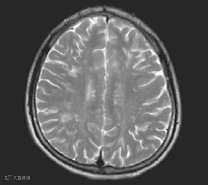

患者,男,17岁,因“反复头痛3年,视物模糊10天”。入院前3年患儿出现反复头痛,不伴发热、咳嗽、抽搐。多次于外院行头颅MRI 显示脑、脊髓、胸髓多发脱髓鞘病变(多处脑组织可见片状不规则异常改变;头颅MRI:颈髓中部可见斑片状异常信号,符合脊髓脱髓鞘病变;颅MRI:脑及胸髓内多发病变)。淋巴细胞亚群示:CD19+20%,CD20+ 17.3%。

左图:头颅MR 示双侧侧脑室旁多个点状、右侧半卵园中心多个片状T2 高信号。右图:头颅MR 示右侧侧脑室顶部多个片状T2 Flare 高信号。